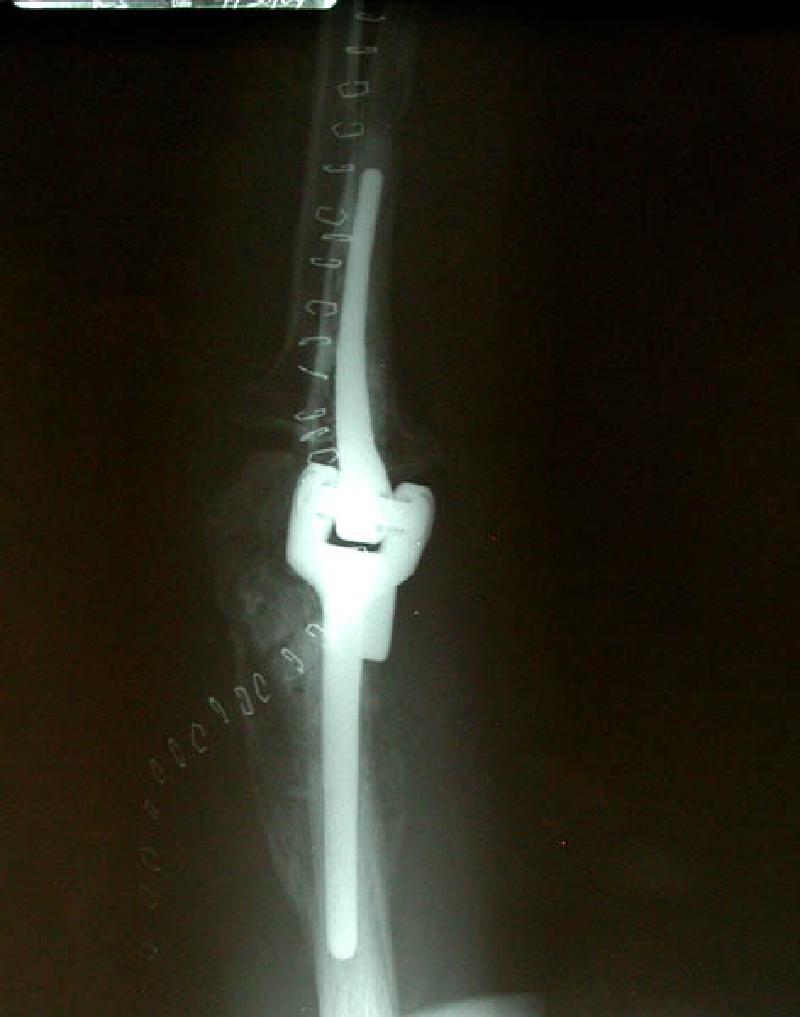

Side and front views of Marla's new artificial elbow joint! You can see the staples that hold the surgical incision closed.